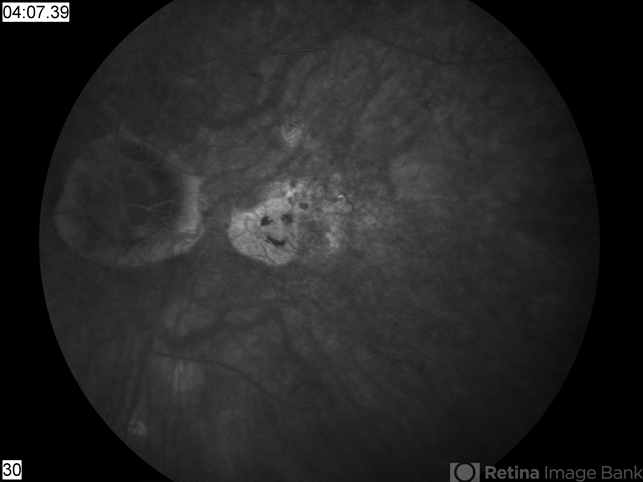

- Macular degeneration with smiley face

- dry age-related macular degeneration (dry AMD)

- AMD, smiley face or Casper the Ghost.